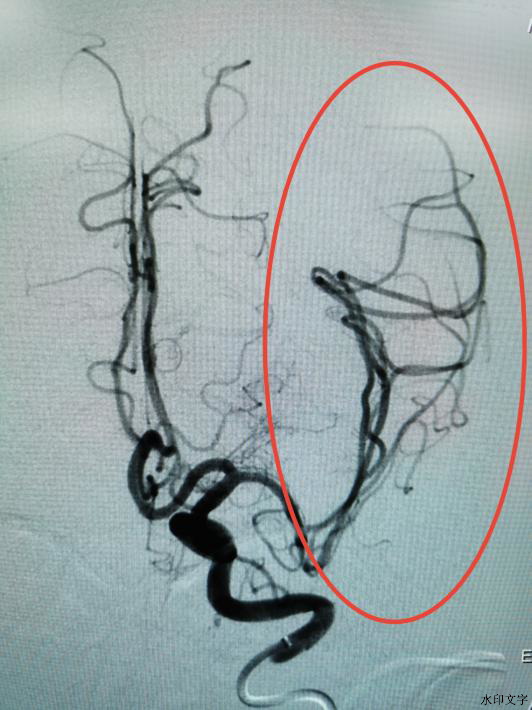

术前大脑中动脉完全堵塞

术后堵塞血管完全打通